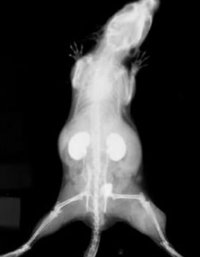

AuroVist 1.9 nm成像結(jié)果展示:

| |

| 靜脈注射AuroVist 1.9nm后小鼠腎臟的顯微CT。 | 活鼠注射AuroVist x射線造影劑后5分鐘成像。 |

| 活體小鼠靜脈注射AuroVist 1.9nm后的腎臟成像: 我們可以發(fā)現(xiàn):小的納米金顆粒從血液中過濾出來,通過腎小球、腎小管進入輸尿管。 | |